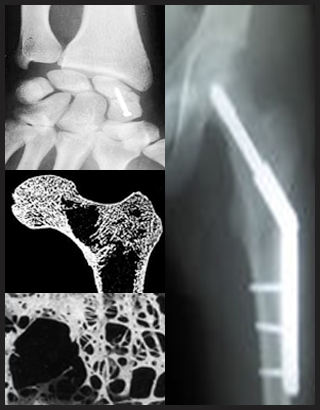

Bone drilling is widely used in many orthopaedic surgery procedures, including those for correcting bone fractures and for joint implantation. Relatively high forces and temperatures experienced during bone drilling can cause significant damage to the bone, such as, and cell death (osteonecrosis). Therefore, a thorough understanding on and predictive thermo-mechanical models for the bone drilling process are needed. The main objective of this research is to develop mechanical and thermal models for the bone drilling process with applications to orthopaedic surgery. A comprehensive investigation including analysis, modeling, and experimentation of thermo-mechanical aspects of bone drilling was performed for the bone drilling process with applications to orthopaedic surgery. The models will enable prediction of drilling forces and temperature distribution in the bone for given drill-bit geometry, drilling conditions, and material characteristics of the bone. The ultimate goal is to improve the outcome of surgical procedures by reducing iatrogenic trauma and invasiveness of the procedure. The oucomes of this research can be applied to robotic surgeries, medical devices, and/or virtual training program for surgeons with applications to surgeries (e.g., orthopaedic surgery, orthodontic srugery, facial surgery, and neurosurgery, etc.).